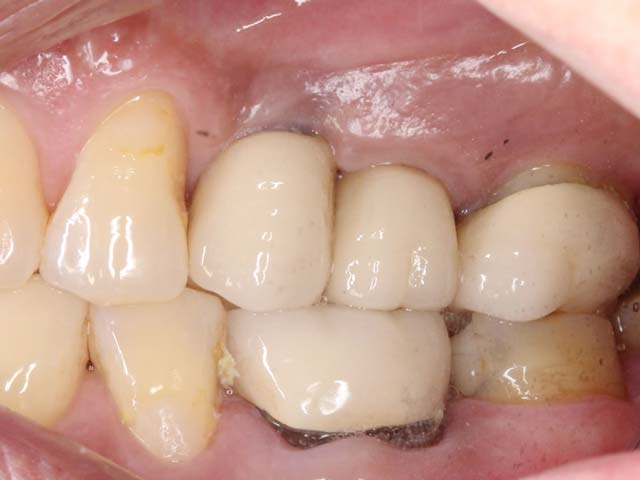

鼻竇增高術(側窗) 首頁 案例分享 人工植牙 鼻竇增高術(側窗) 鼻竇增高術(側窗) 製作多年的牙橋,牙根斷裂,發炎 鼻竇增高術 側面開窗 抬高鼻竇 鼻竇增高術 置入骨粉 覆蓋再生膜,保護骨粉 術後追蹤,傷口良好 裝戴正式假牙 完成 8年追蹤 左上牙根斷裂 植牙重建 九年追蹤